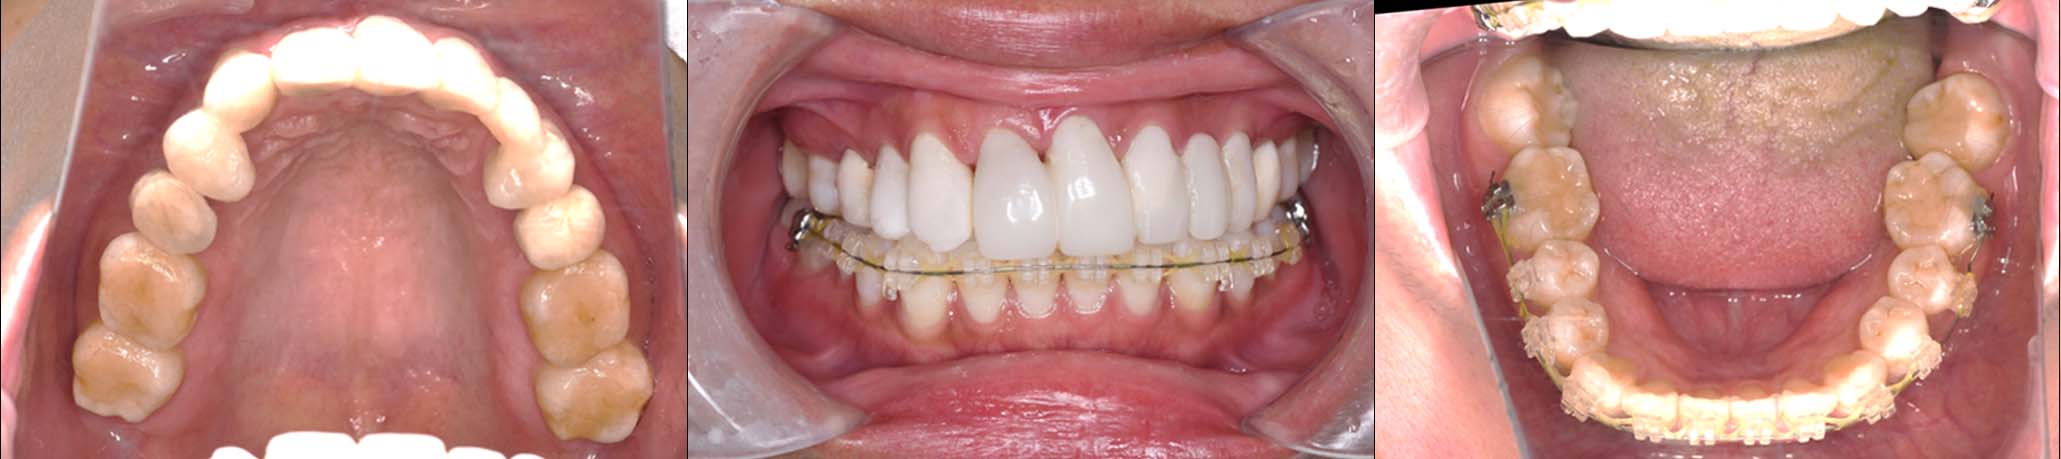

2024年 10月 下顎MTM開始

2024年 10月10日

10月21日

11月7日

11月28日

12月16日

12月23日

1月9日

1月30日

2月20日

3月13日

4月24日

9月25日